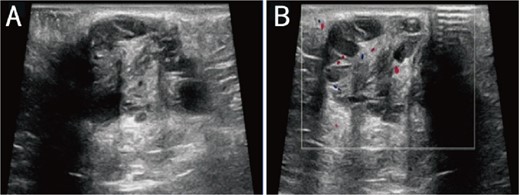

A 38-year-old married female patient presented with a lump near her anus 10 years ago, without apparent cause or symptoms such as redness, swelling, heat, or pain, nor cough, abdominal pain, or diarrhea. No specific treatment was administered. The patient now reports that the lump has grown larger and is accompanied by increasing swelling and discomfort. Seeking further diagnosis and treatment, she visited our outpatient department, where she was admitted with the condition “perianal lump.” Physical examination revealed a body temperature of 36.5°C, pulse rate of 86 beats/min, respiratory rate of 19 beats/min, and a blood pressure of 134/85 mmHg. Admission symptoms include perianal swelling and pain, with itching; no signs of fever, chills, rupture, or pus discharge; bowel movements once or twice daily, and normal urination. The patient has one child and underwent a lateral epidural resection 12 years ago due to natural childbirth. Specialist examination revealed a 4-cm lump with a hard texture at 7–11 o’clock next to the anus, and a radial surgical incision at the 7 o’clock anal margin. Digital rectal examination found no lump, depression, or induration in the anus, and no blood on fingertips. The initial diagnosis was a perianal lump. Auxiliary examinations included ultrasound, which revealed a 4-cm lump in the subcutaneous soft tissue near the anus with minor blood flow signals within and around it, suggestive of an inflammatory lesion (Fig. 1A and B); and pelvic MRI, which suggested a left perianal lump consistent with a perianal abscess (Fig. 2A and B). Under spinal anesthesia, the perianal lump was removed, and postoperative pathology confirmed the presence of endometriosis (Fig. 3).

Ultrasound: (A) 2D ultrasound shows a mixed echo with a range of about 4 cm in the subcutaneous soft tissue around the left side of the anus, presenting as cystic-solid; (B) color doppler shows a small amount of punctate blood flow signal inside and around the mixed echo.

PE represents a specific type of endometriosis, with related studies reporting that iatrogenic implantation is closely linked to the development of endometriotic lesions in perineal lateral incision scars [6]. PE exhibits symptoms similar to those of perianal abscesses, with both conditions originating around the anus. These conditions are clinically rare, often leading to misdiagnosis due to a lack of understanding among clinicians. In contrast to perianal abscesses, PE typically presents as recurrent perianal masses accompanied by cyclical pain, with the masses enlarging during menstruation and subsequently shrinking or disappearing thereafter [7, 8]. Patients often have a history of perineal lacerations or episiotomy, with surgical scars typically visible on specialized examinations. Anorectal examinations reveal no signs of anal sinus infection [9]. Ultrasonography demonstrates heterogeneous hypoechoic masses with punctuate or branching blood flow signals [10]. MRI exhibits a sensitivity of 90%–92% and a specificity of 91%–98% for the diagnosis of PE. MRI not only precisely locates the lesion but also outlines its extent, enabling differentiation from various anorectal conditions, thereby greatly aiding in the disease’s diagnosis [11]. Histopathological examination serves as the definitive diagnostic method for this condition, requiring the microscopic identification of two out of three components: endometrial stromal cells, glands, and hemosiderin, to confirm the diagnosis [12].